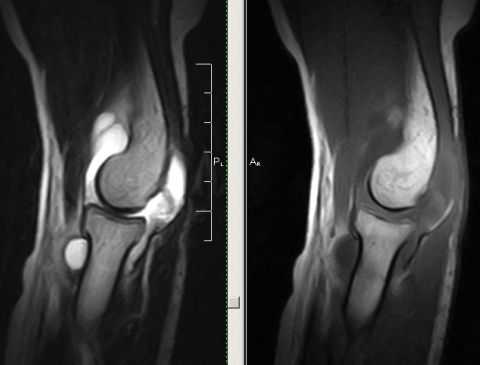

Вывих локтевого сустава на МРТ

Вывих локтевого сустава по частоте распространенности и выявлений уступает только повреждению плеча или пальцев. Вывих локтевого сустава, как правило, становится следствием падения пациента на вытянутую руку или приобретается в результате автомобильной аварии. Некоторые заболевания (артрит и артроз), вызывающие повреждения суставов, также могут увеличить вероятность вывиха локтевого сустава. В случае если пациент получил внутрисуставный перелом, при котором происходит повреждение связочного аппарата, желательно пройти магнитно-резонансное исследование. МРТ локтевого сустава даст представление об изменениях в суставе, вызванных переломом, в том числе о состоянии хряща, связок, окружающих тканей, полную информацию о которых нельзя получить при КТ-диагностике.

При травмах локтевого сустава могут быть повреждены его сосуды, мышцы, нервы, капсулы, связки, сухожилия, синовиальные сумки и другие важные структуры. Перечисленные повреждения могут повлечь за собой ограничение движения пациента и требуют вправления кости и безотлагательного накладывания гипса/фиксирующей повязки.